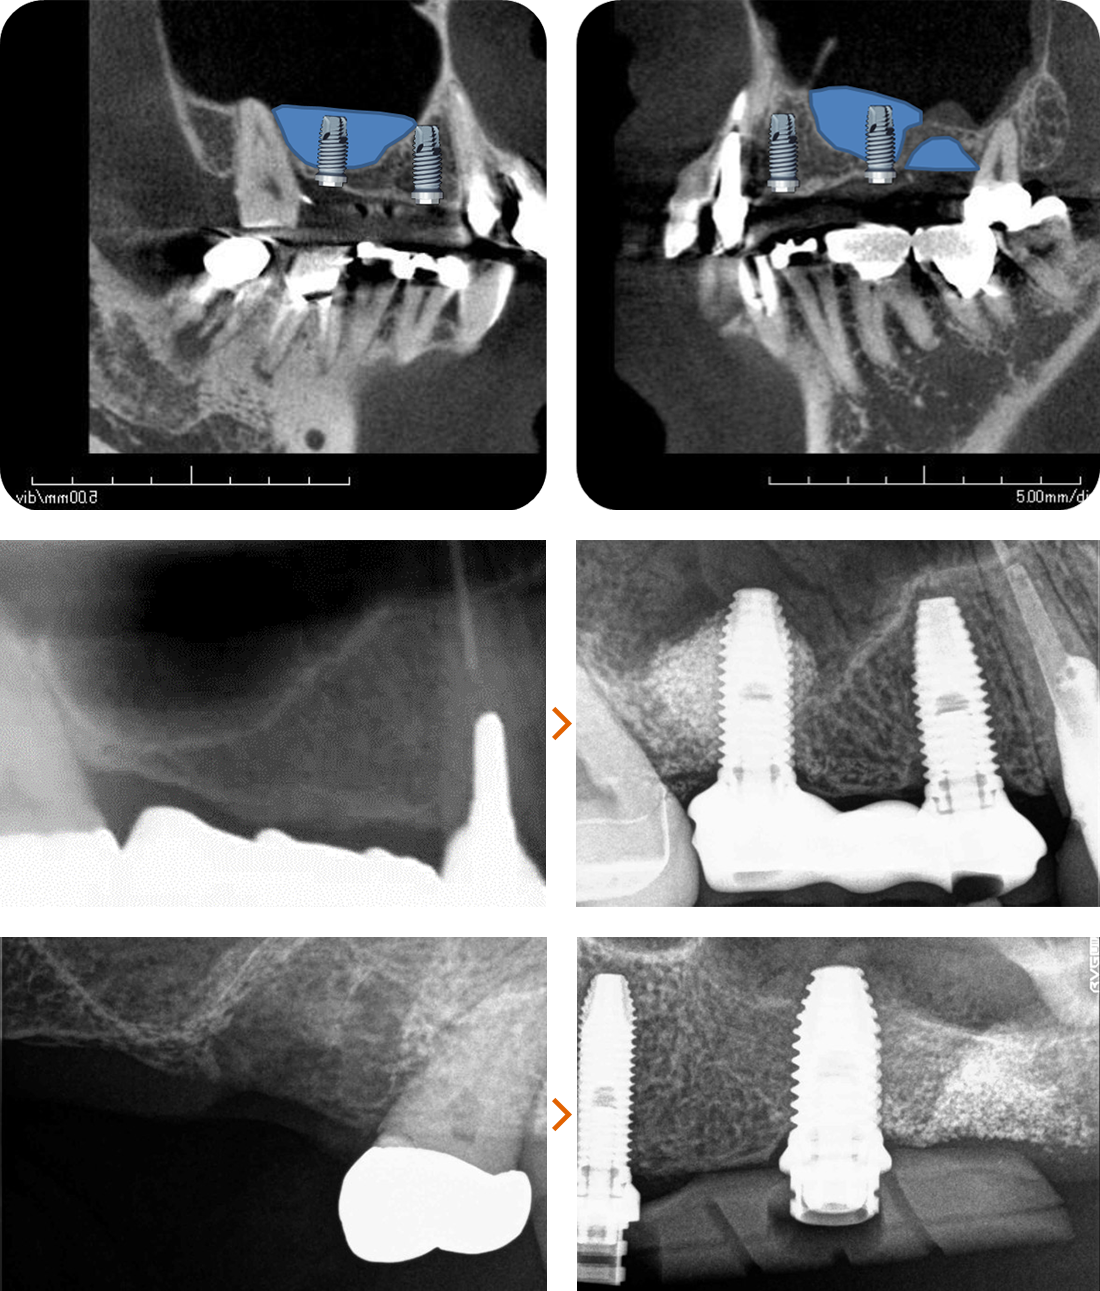

治療症例 Case3

Treatment cases

ご相談内容

- 上の左右2番目の歯と尖っている前歯が気になる

- 歯の形を治したい

- 歯の色をきれいにしたい

ホワイトニングで全体的に白くした後、その色に合わせて被せ物を作っていきます。

治療内容

模型を作成して最終的な形を模索します。

ファイバーコアで神経のない歯に土台を作ります。

ファイバーコアは保険治療で使われるメタルコアと異なり白く、被せ物が透けて黒く見えません。

土台になる歯の形を整えて最終的な形の模型を作ります。

治療後

白く明るい口元になりました。